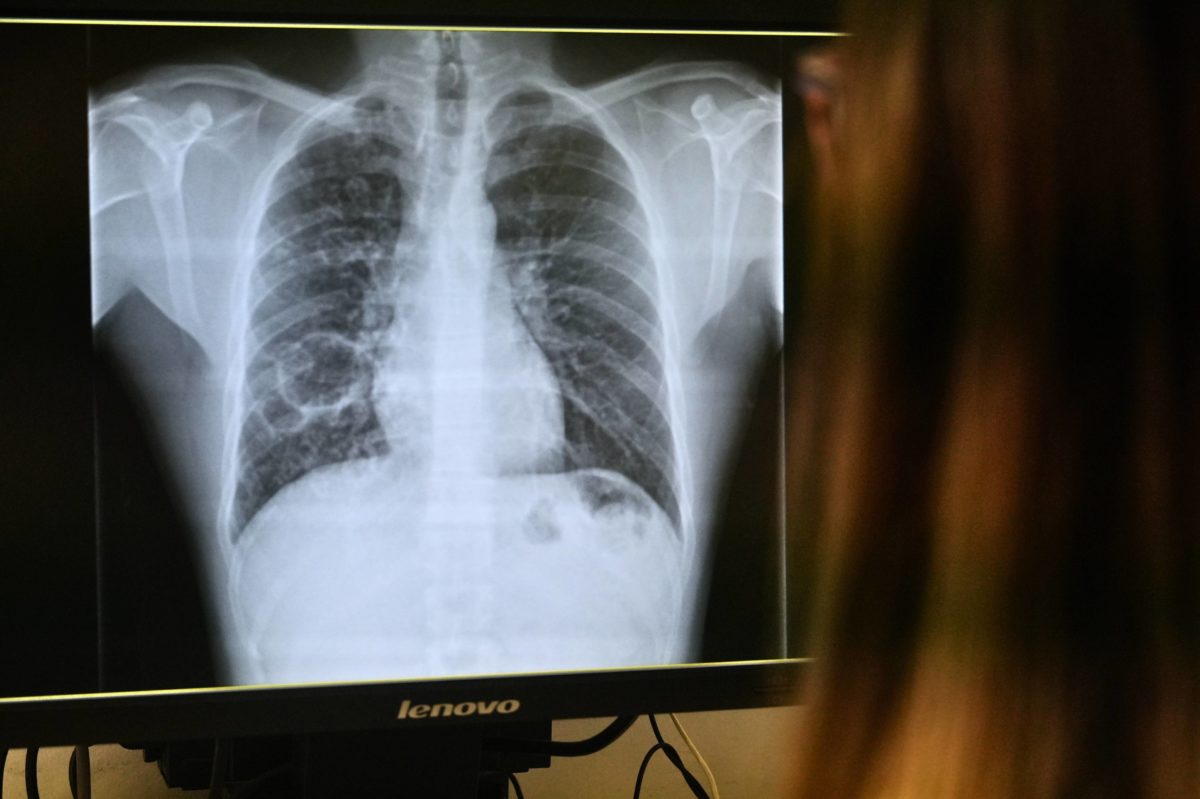

La tuberculosi afecta principalment el pulmó encara que també pot tenir una afectació extrapulmonar. Només les persones amb afectació pulmonar activa són transmissibles, ja que és al pulmó on el bacteri es multiplica en gran quantitat i es pot expulsar a l’aire.